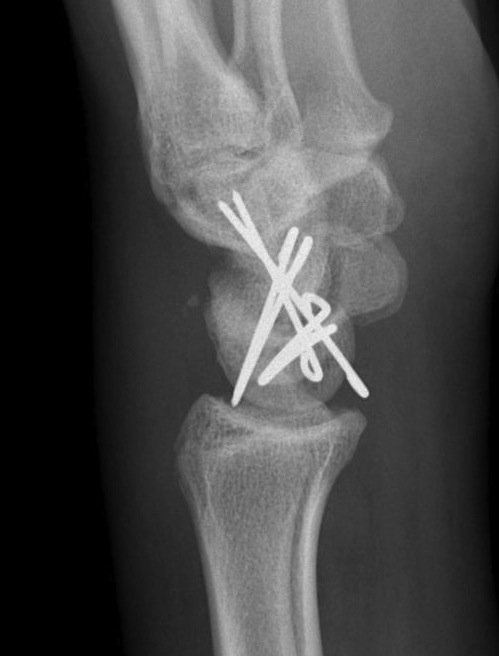

Technique

Dorsal approach

- 3/4 extensor compartment

- mobilise EPL laterally

- capsulotomy: T shaped or Berger (open dorsal between DRC and DIC ligaments)

- K wire joysticks in scaphoid and lunate and reduce

- K wires scaphocapitate / scapholunate / lunatetriquetral (areas of ligament rupture)

Perilunate fracture-dislocations / Trans-scaphoid perilunate

- ORIF scaphoid fracture with headless compression screws

- assess stability of scapho-capitate and scapholunte joint (often ligaments intact and stable)

- K wires lunate-triquetral +/-